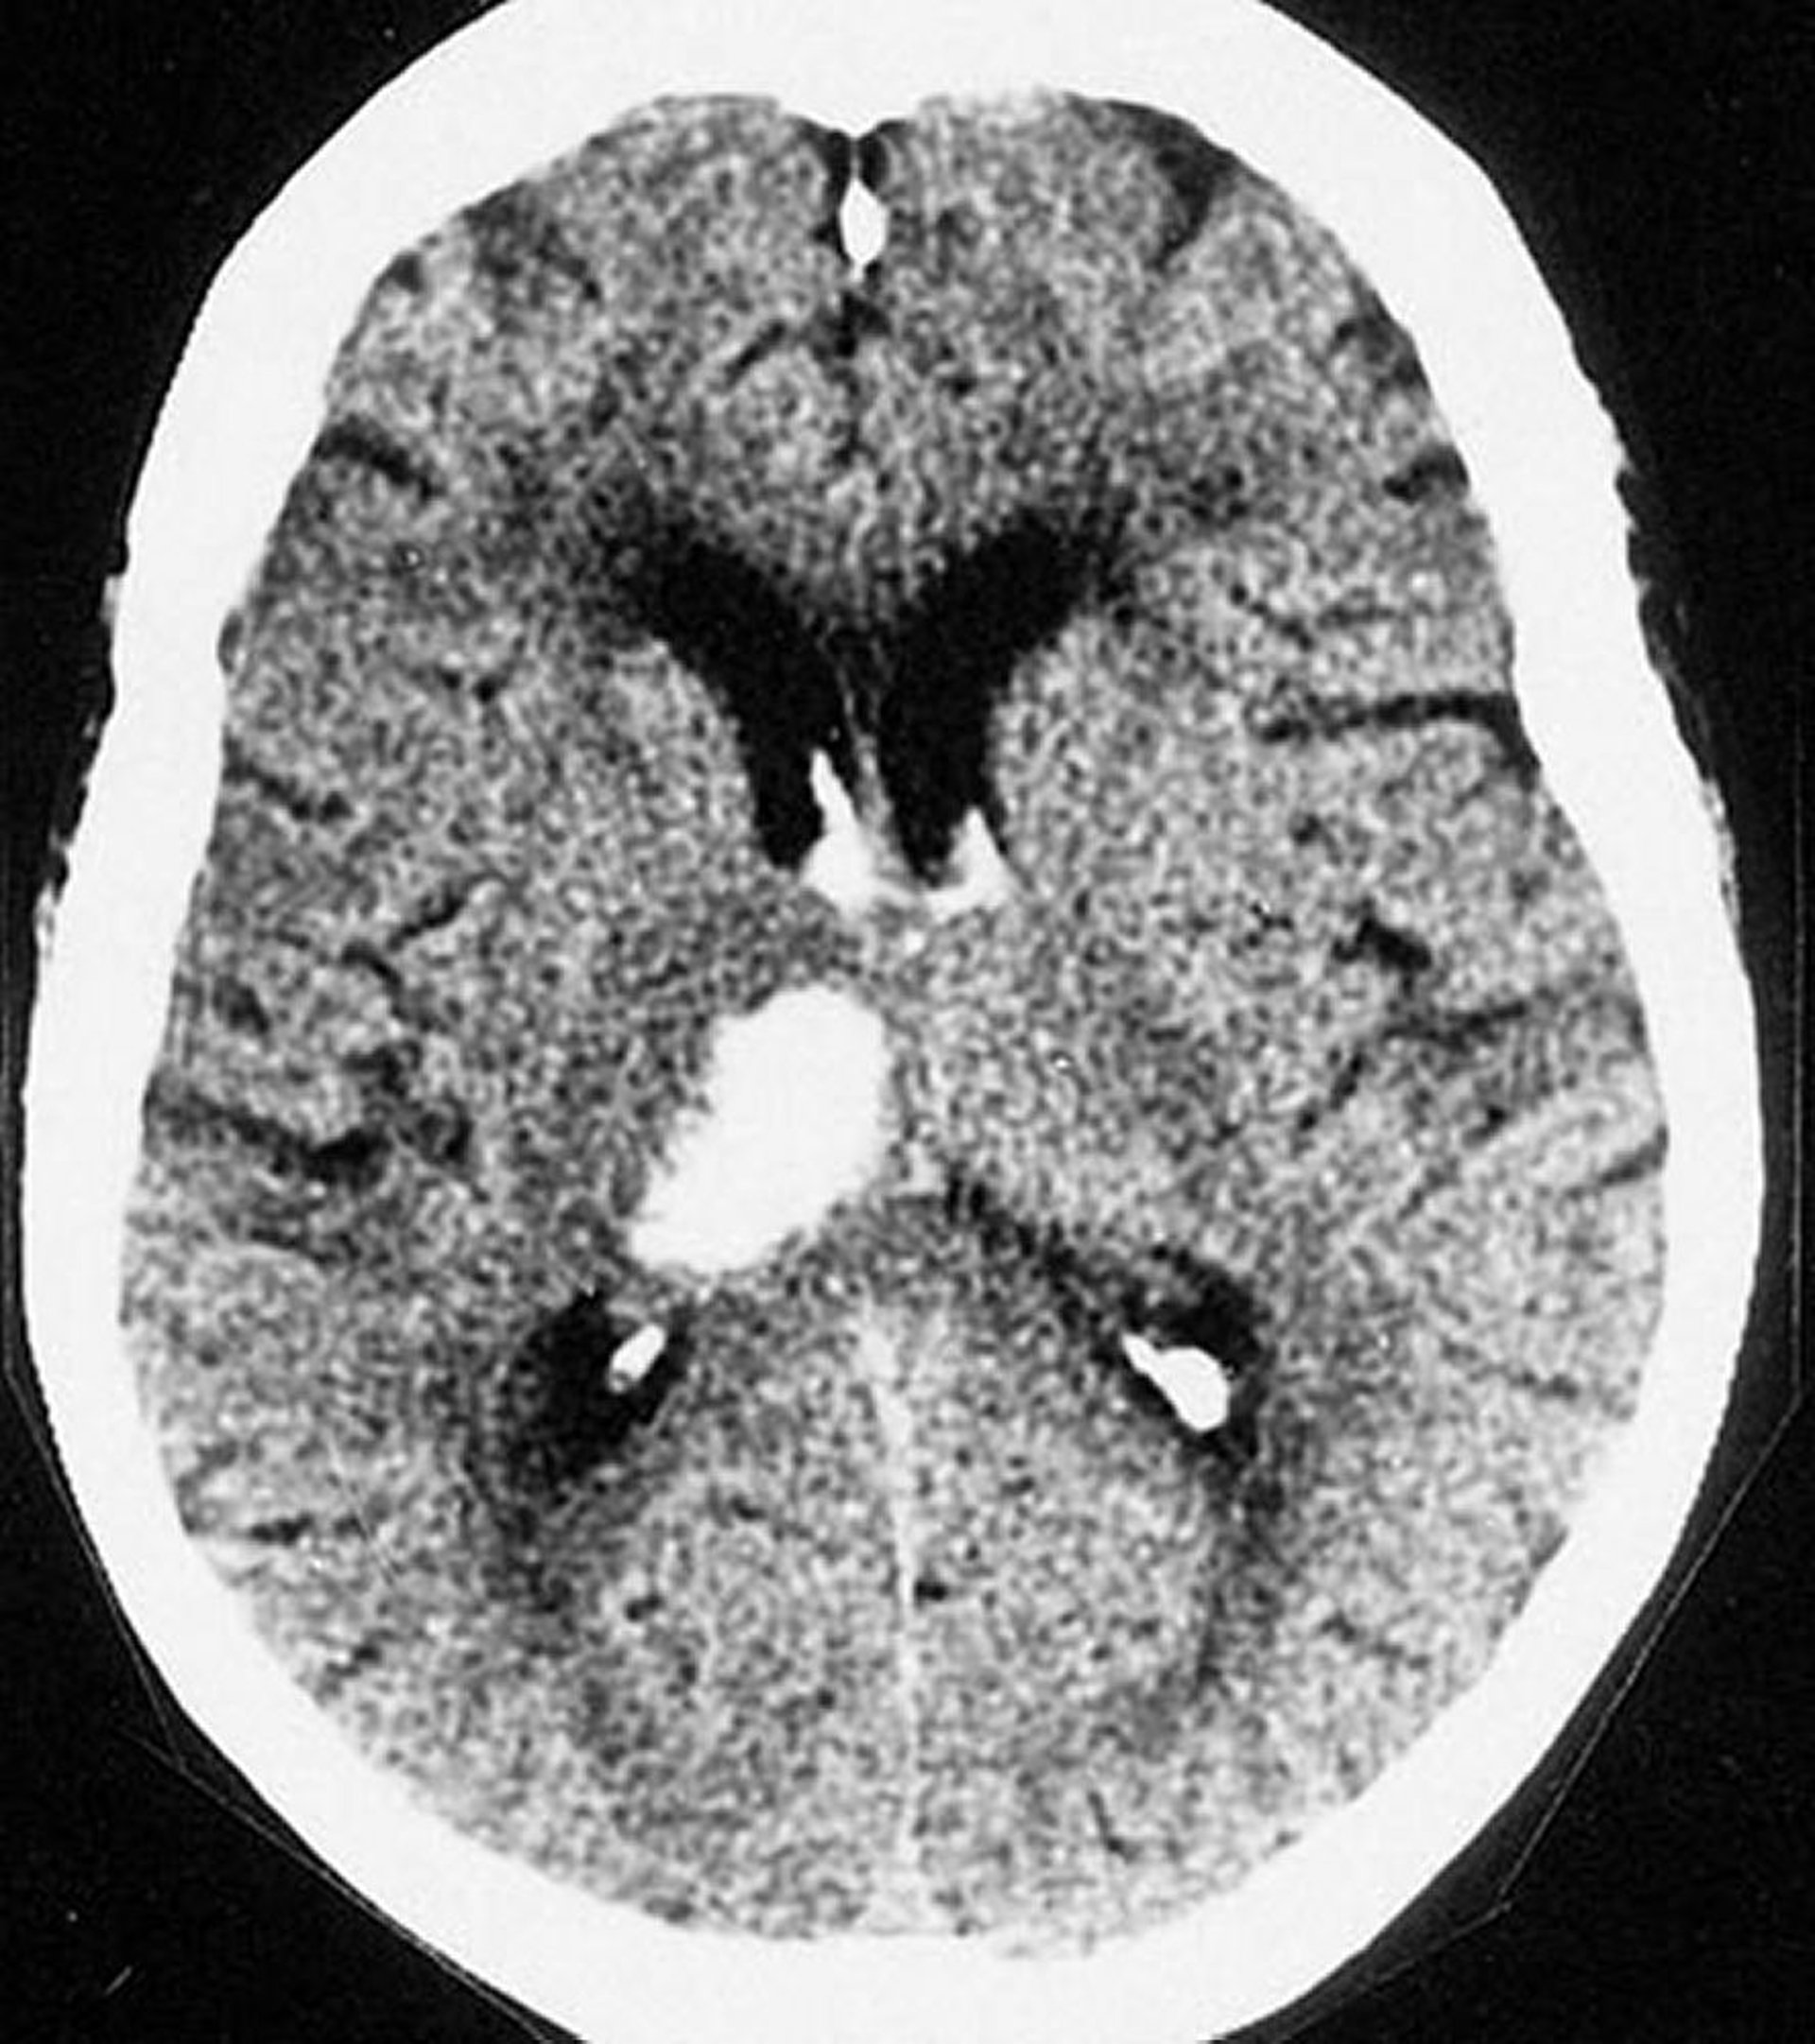

Intrazerebrale Thalamusblutung

Diese CT-Aufnahme zeigt eine Blutung im Thalamus. Intrazerebrale Blutungen treten am häufigsten im Thalamus und in den Basalganglien auf.

By permission of the publisher. From Furie K, et al. In Atlas of Clinical Neurology. Edited by RN Rosenberg. Philadelphia, Current Medicine, 2002.